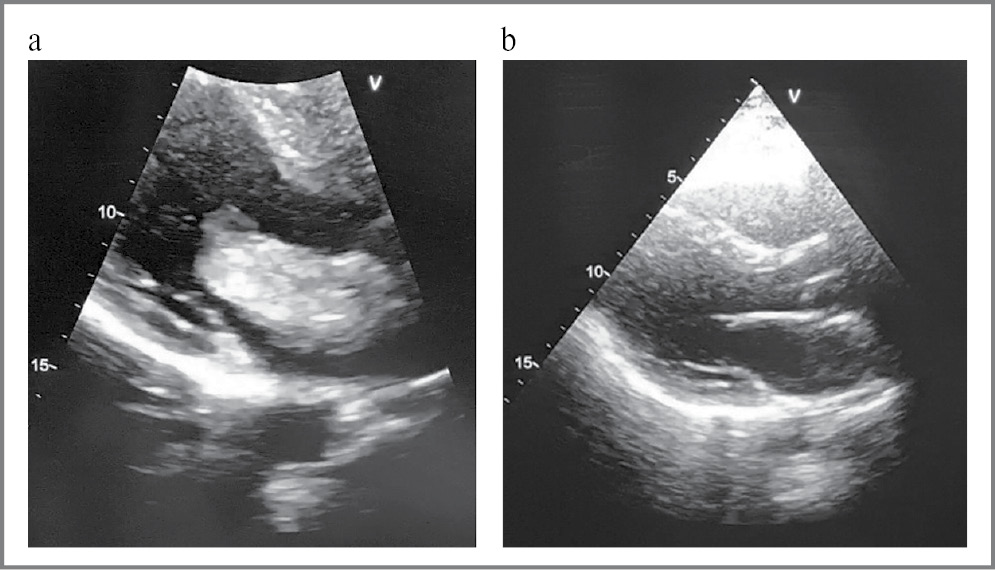

По данным ЭхоКС, выполненной в условиях кардиохирургического центра, выявлено дополнительное подвижное образование в полости ЛП размером 54×27 мм, фиксированное к центральной части межпредсердной перегородки (миксома), в диастолу пролабирующее в полость ЛЖ, с признаками обструкции без значимого градиента обструкции на митральном клапане, представленное на рис. 4.

Рис. 4. ЭхоКС: а – миксома в области ЛП с пролабированием в полость ЛЖ; b – состояние после удаления миксомы.

Fig. 4. Echocardioscopy: a – myxoma in the region of the left atrium with prolapse into the cavity of the left ventricle; b – condition after removal of myxoma.